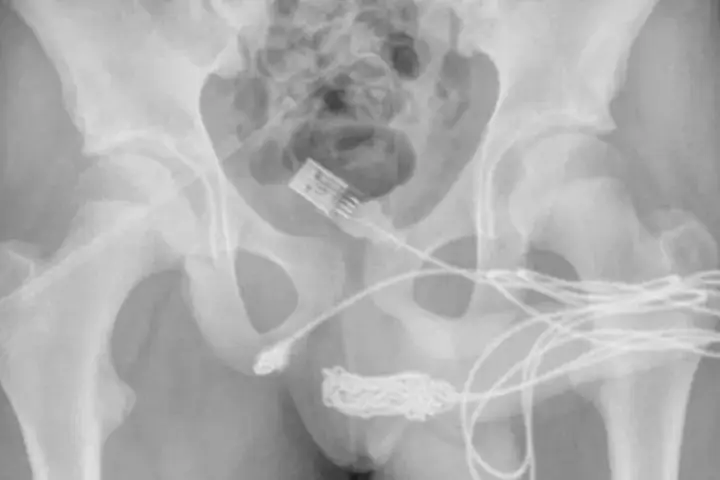

Após alguns Raio-X os médicos constataram que o fio havia dado um nó dentro do corpo do rapaz e só poderia ser removido cirurgicamente, através de uma incisão entre o pênis e o ânus do adolescente.

Um adolescente de 15 anos teve que ser submetido à uma cirurgia de emergência após ficar com um cabo USB preso dentro da uretra após, segundo ele, utilizar o fio para medir o interior do próprio pênis.

Após duas tentativas fracassadas de remover o cabo, o rapaz desistiu e acabou com ambas as extremidades do fio penduradas para fora do órgão.